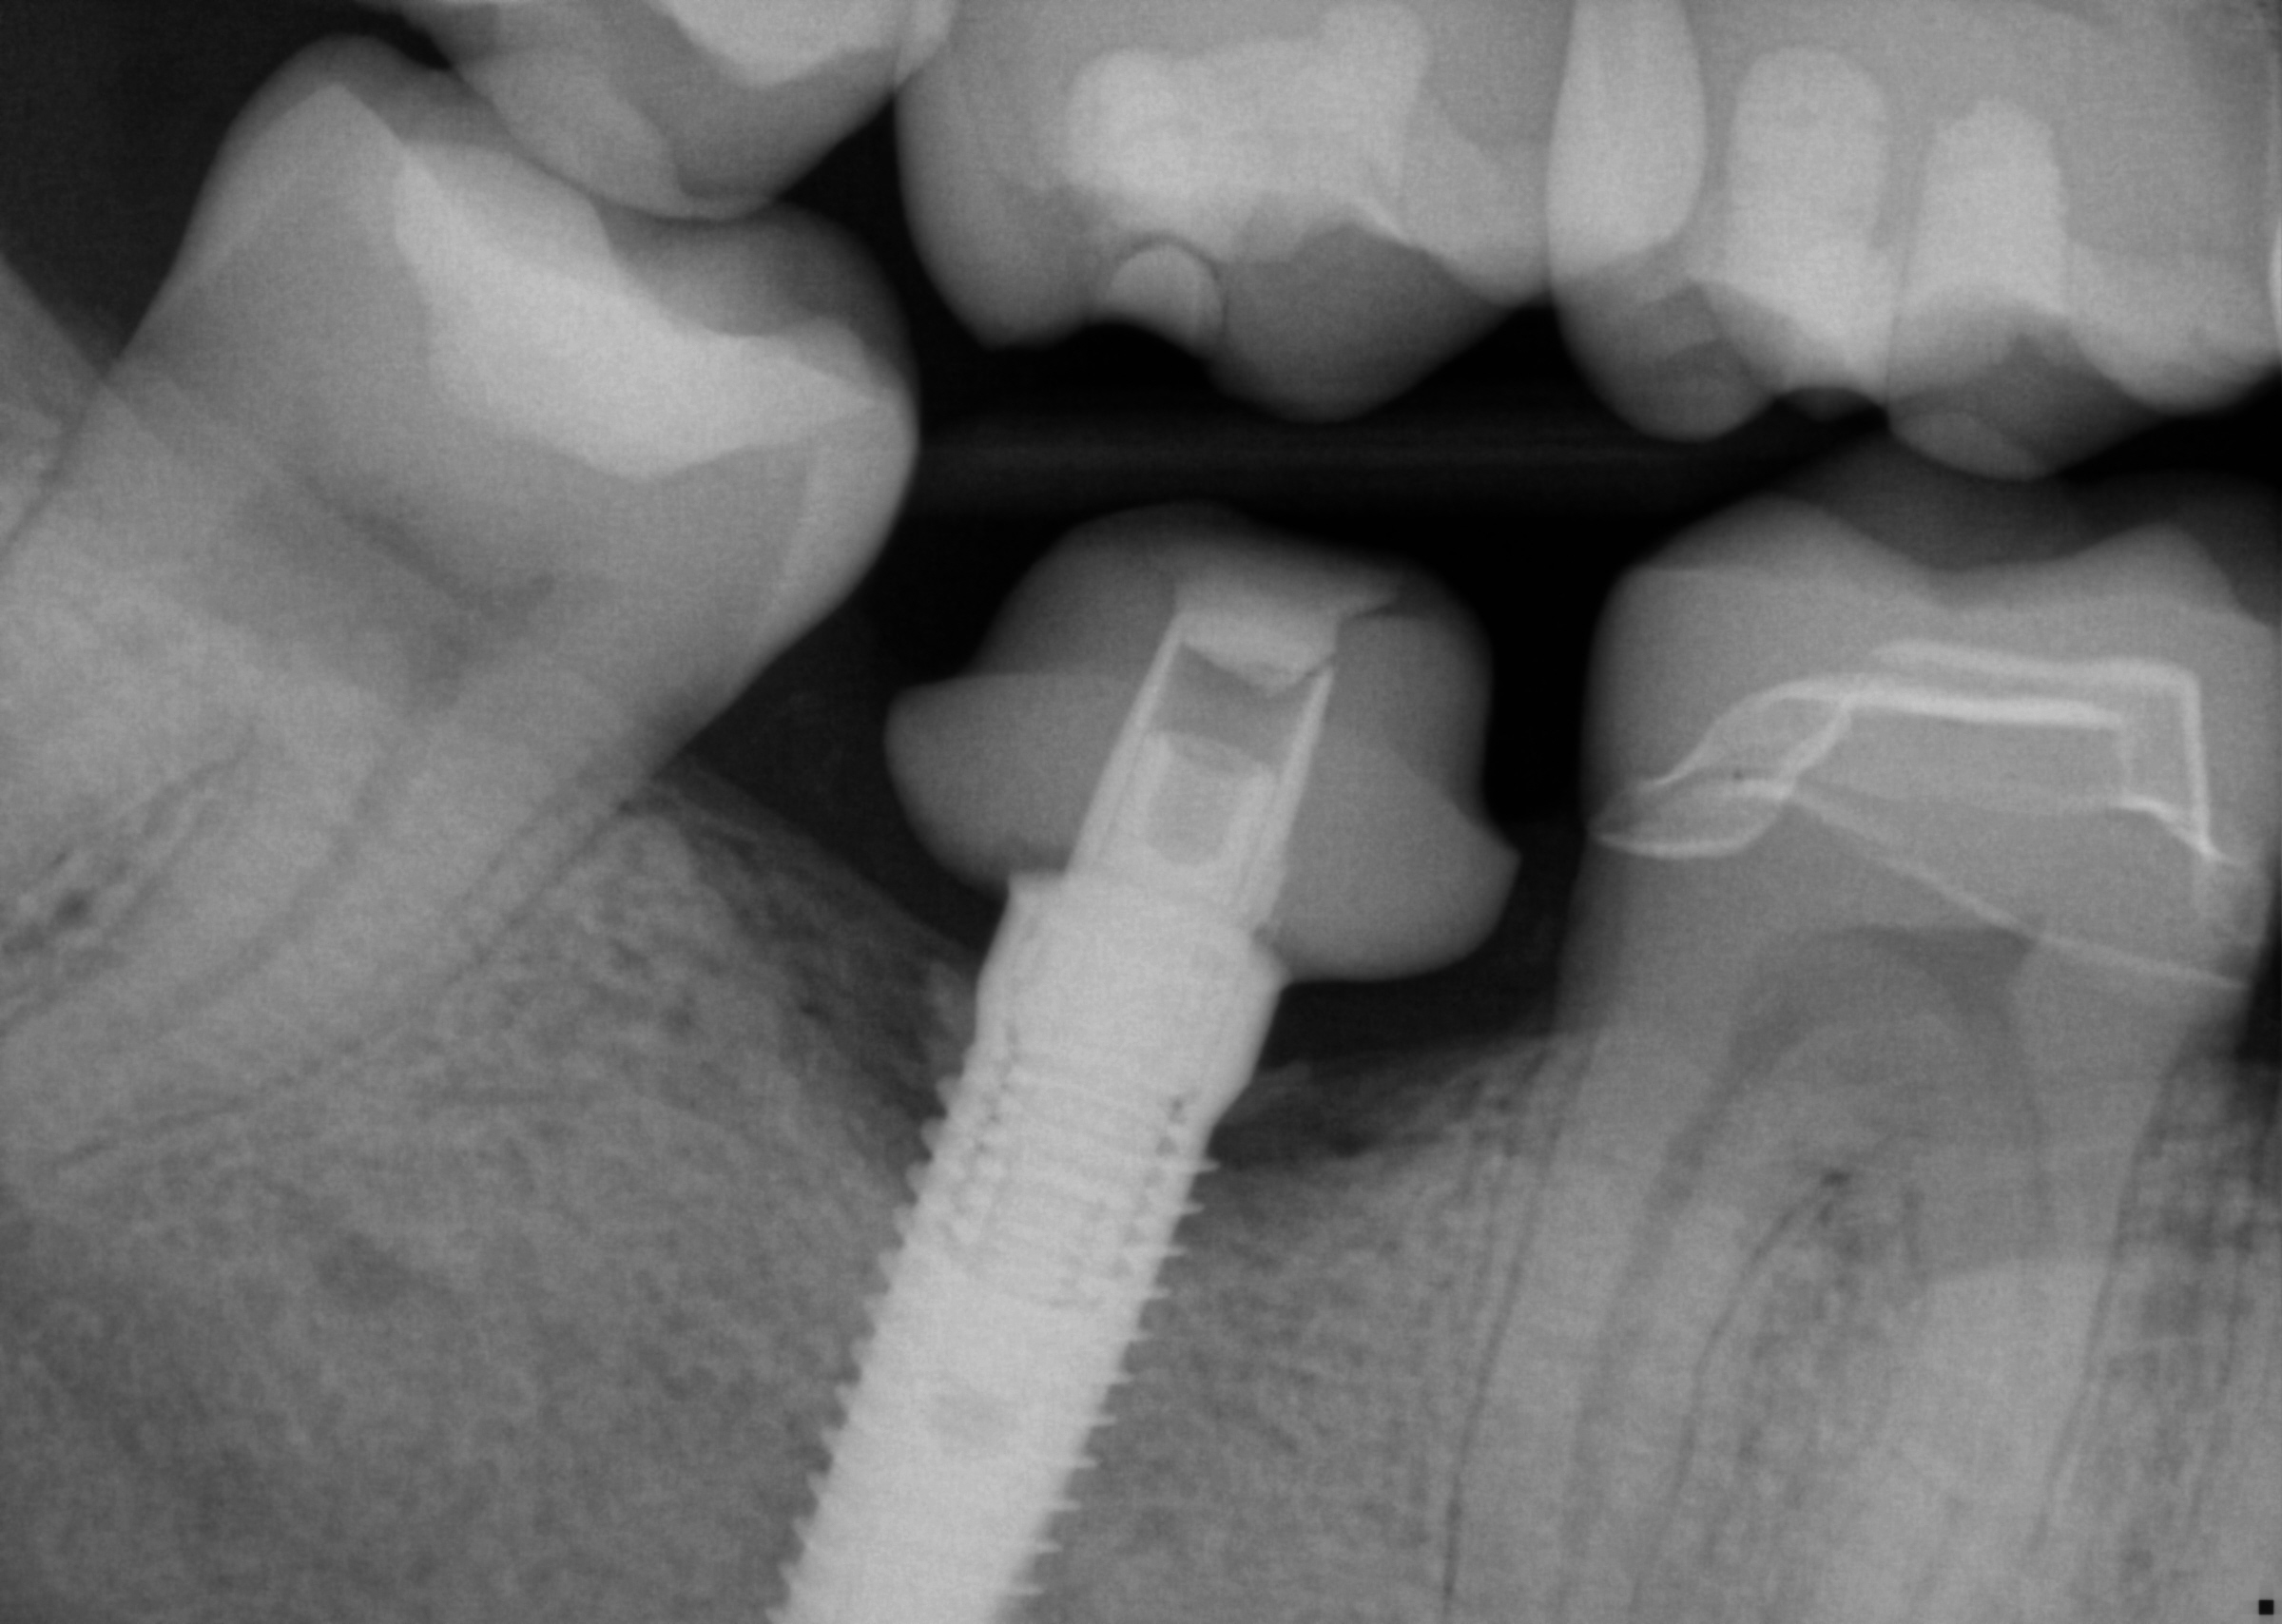

This implant was initially placed at the crest of the ridge in 2012. its placement did not allow proper emergence profile and subsequently lost bone around the head of the implant by 2015. The lack of blood flow to the crest of the bone at the cortical plate certainly could have contributed to its demise. By 2015, the bacteria trap forced a new restoration to be placed which also ultimately lead to chronic inflammation due to improper contours. The implant itself was well integrated and the decision was made to remove the top 3-5 mm of the implant and treat it as a cast post and core.

Post op x-rays to verify seat and no excess resin after flap was raised to clinically visualize that there is no excess cement